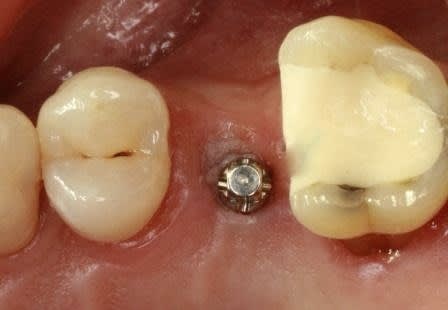

> Voici le cas en image

> Mon doute portait donc sur la face vestibulaire de l'implant en place de 43.

> Implant4.5*11 Astra

Serrage manuel, sans lambeau. Extraction implantation immédiate

le 4.5*11 me semblait convenable. J'avais peur que si je metais du 4*11 l'espace entre les cretes vestibulaires et l'implant allait creer une recession si je ne comblait pas ce vide

Rappelons qu'en mesurant j'ai 1.25 mm d'os au final et pas 0.5-0.8mm

merci pour tes réponses, pour ma part (expérience avec plus de 600 implantation immédiate) je ne pense pas qu'il va y avoir une résorption, car pas de lambeau et tu n'as pas mis de trop grande pression sur l'os buccal.Un exemple ci dessous implantation ( 4 semaines après extraction) avec un 4.5 que (oui déjà mis dans un autre post).J'ai d'autres exemples similaires en extraction implantation immédiate mais avec des implants 3.5mm.Si l'espace entre l'implant et l'os buccal est plus grand que 1mm j'ajoute du collagène et de l'acide hyaluronique pour accélérer la régénération.

dernière radio à un an après cémentation de la couronne.

Ce qui est non négligeable est d'avoir une stabilité primaire d'un minimum de 35Ncm et pas plus de 70Ncm.